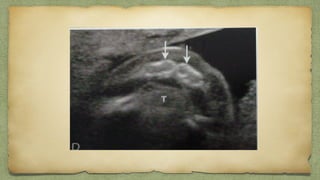

Spina Bifida

Spina

bifida

w

ith

m

eningom

ylocele

Overlying skin at

Sacrum is absent